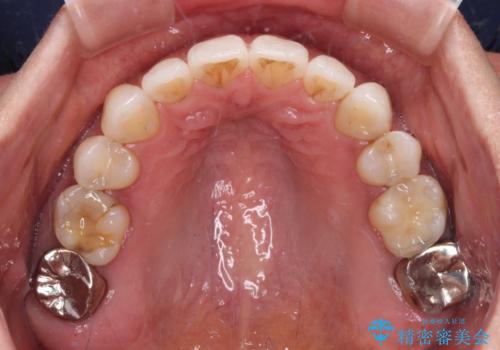

- 下顎前歯を中心に、以前行った矯正治療の後戻りが気になるとのことで来院された患者様です。

後戻りは軽度であったため、インビザライン・ライトにて治療を行うこととしました。

矯正治療後は、再度後戻りすることを極力回避するために、下顎前歯の舌側を細いワイヤーを用いて保定することとしました。